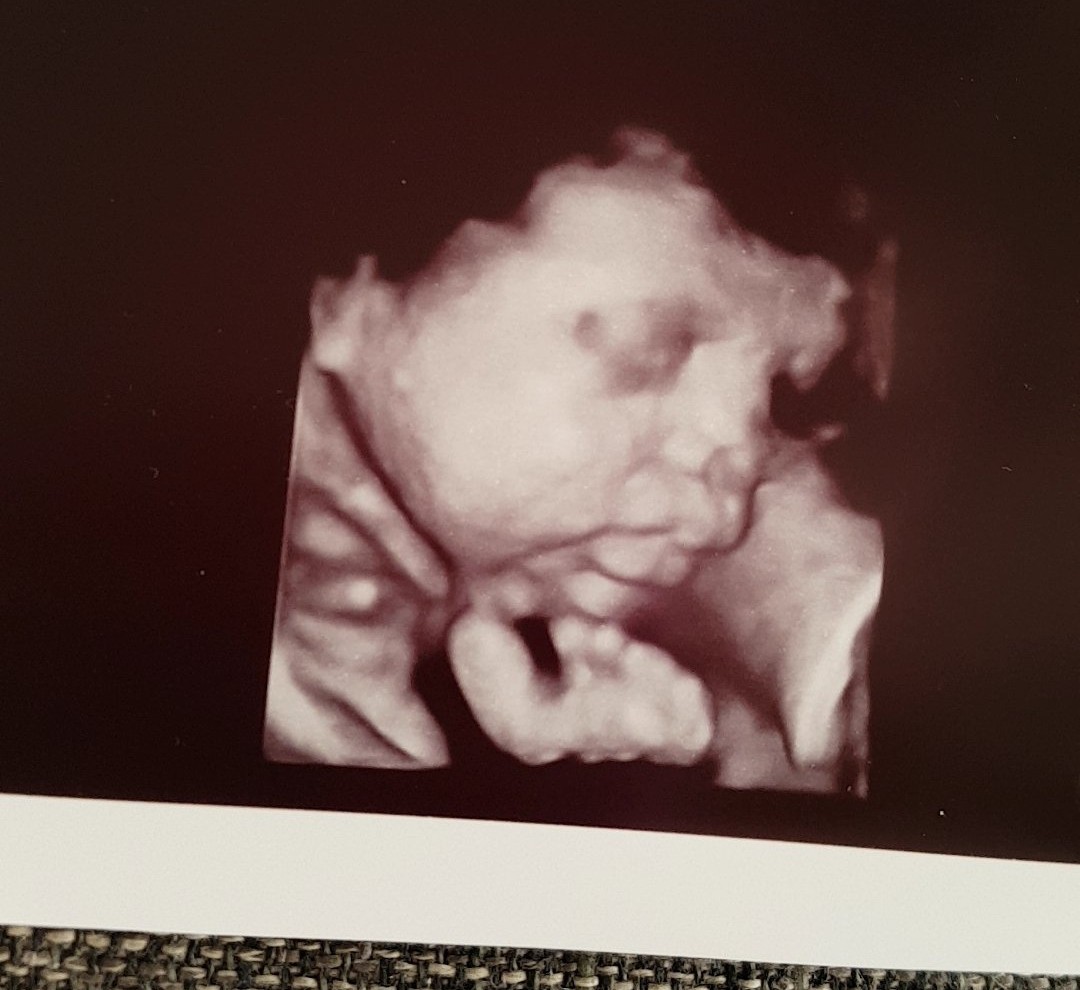

Witam a dziękuję dobrze się miewa .

Już niedługo się zobaczymy pozdrawiam .

A jak u Ciebie ?Zobacz załącznik 831052